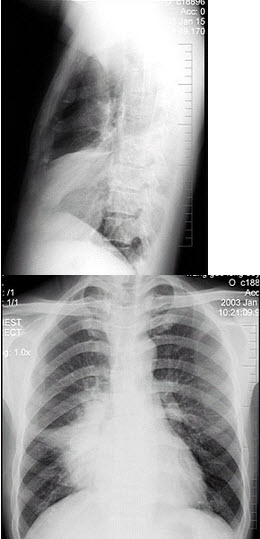

10、单项选择题

男性,45岁,有糖尿病史,突起寒战、高热,咳嗽,快脓性痰,伴胸痛2天,X线显示双肺实变,其中可见多个液气囊腔(如图),最可能的诊断是()

A.葡萄球菌肺炎

B.肺炎支原体肺炎

C.肺炎链球菌肺炎

D.肺炎衣原体肺炎

E.病毒性肺炎